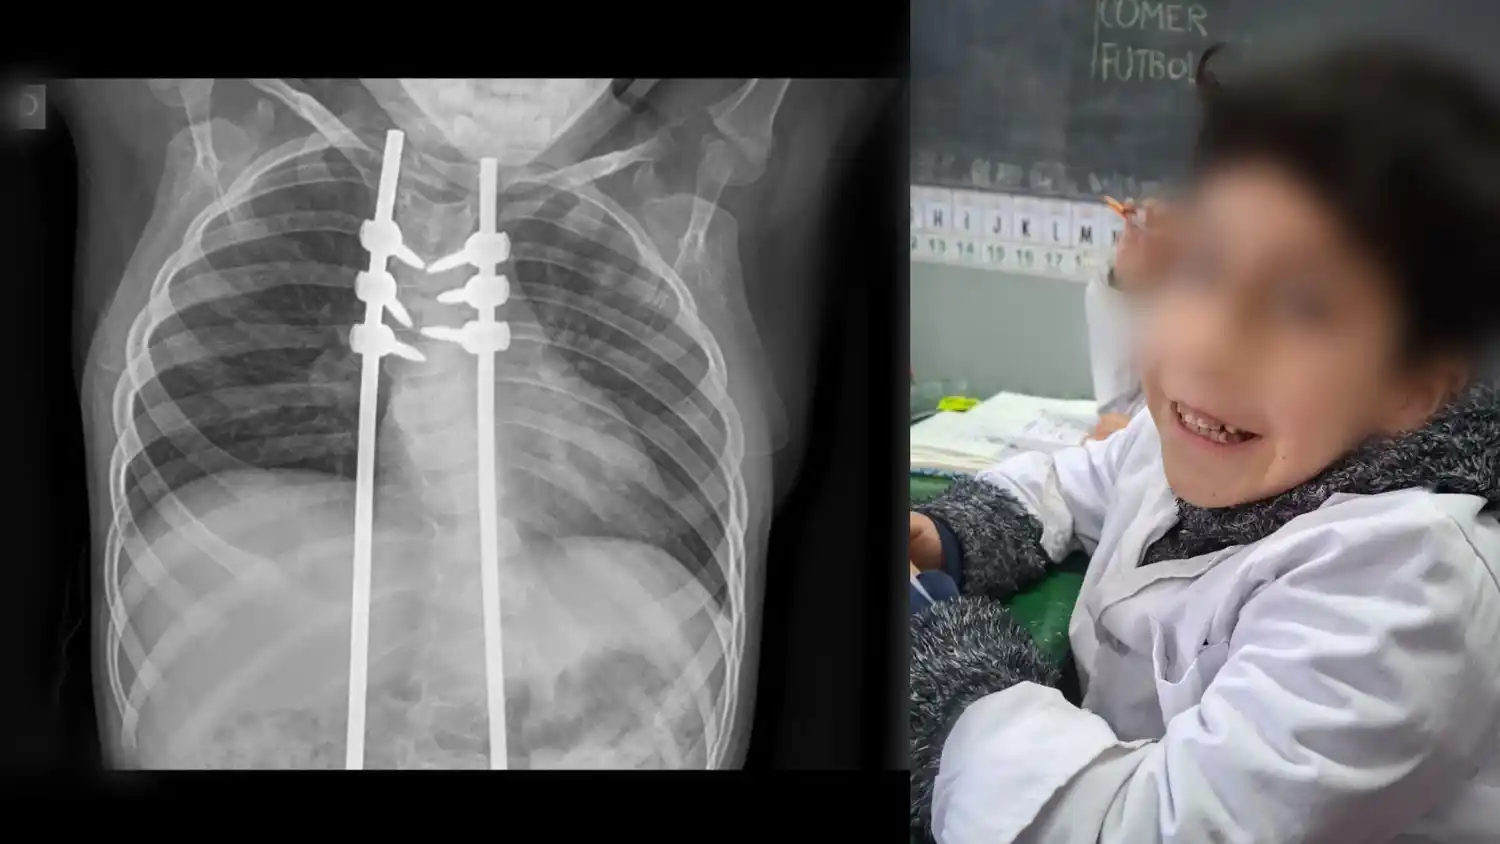

Desde la escuela destacan la contención brindada por maestras y directivos, asiste a una colegio común y articula con la escuela N° 501, pero el acompañamiento resulta indispensable por el leve retraso madurativo de Julián y su condición física: “hace dos años fue operado de la columna y no puede exponerse a golpes o caídas”.